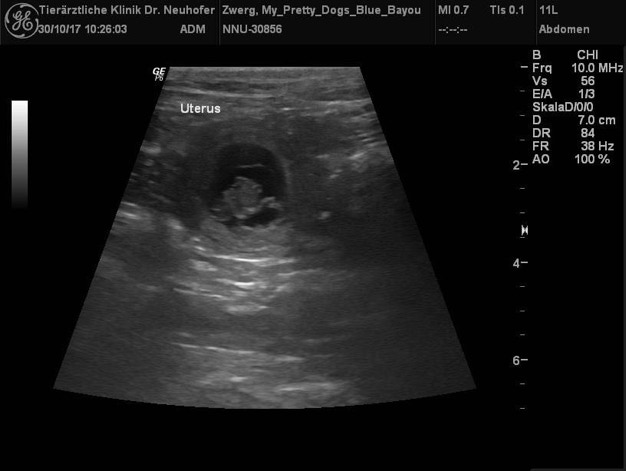

Es hat geklappt!!!! RTCH2 JB Black Saphires Take a Chance und

Ch. My Pretty Dogs Blue Bayou erwarten ebenfalls wundervolle Welpen in Bi und Tri um den 5. Dezember herum.

Blue Bayou und ich waren am 2.10. in Dolgesheim beim Rüden Chance. Die beiden haben sich auf Anhieb verstanden und Hochzeit gefeiert.

Nun heißt es warten und Daumen drücken.